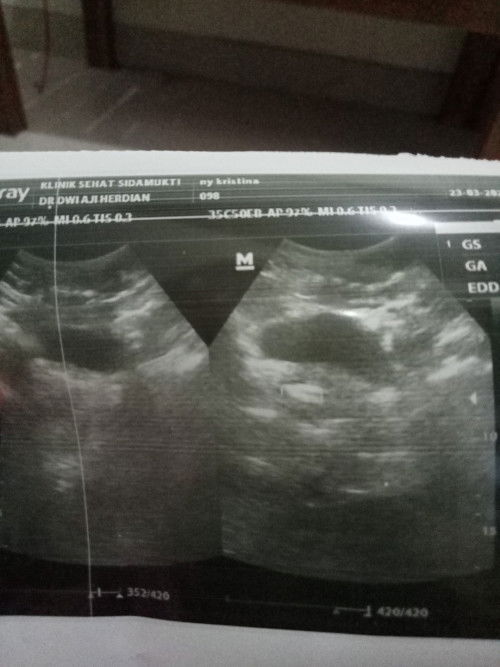

ini hasil usgnya

USG keminggu 8 kok blum klihatan yah.

USG di Minggu 8

Bun kalau di hitung dari hpht sy usg transvaginal di umur 9mgg tapi kantung sm janin nya belum kelihatan,, sebulan kemudian balik lagi udh ada kt dokter usia nya 8mgg skrg😭

klu aku di hitung dri hpht harusnya 9minggu,TPI knpa pas kmarin di USG ini msih kecil bngt blum klihtn pling Bru 5mingguan Bun...kan aku jdi bingung.dri situ aku kepikiran trus smpe gak bisa tidur.

kantongnya belum keliatan juga kak?

Belum ada djj?

blum Bu,,Mlah dokternya bingung